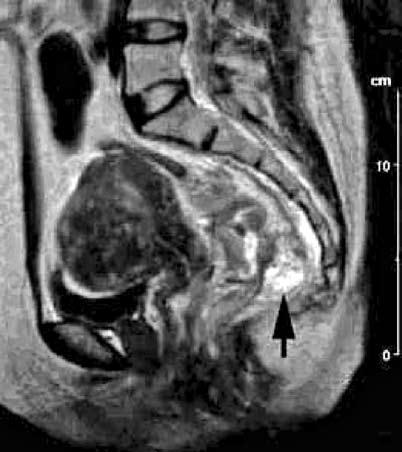

Компьютерная томография – довольно чувствительный метод в диагностике отдаленных метастазов ректального рака (до 98 %). Наиболее частыми из них являются метастазы в печень, которые визуализируются в виде множественных (реже одиночных) очагов пониженной плотности, обычно округлой формы, структура их неоднородная (из‑за наличия участков деструкции). Применение магнитно‑резонансной томографии (МРТ) позволяет с достаточно высокой точностью (более 80 %) определить боковое распространения опухоли, визуализировать взаимоотношение фронта опухолевой инвазии с мезоректальной клетчаткой и собственной фасцией прямой кишки, определить степень распространенности процесса относительно фасциально‑мышечных структур тазового дна (рис. 212). Кроме того, при этом исследовании возможно определение степени поражения лимфатических узлов. Для этого используют вещества с парамагнетической активностью. Непосредственно над зубчатой линией в подслизистый слой, после предварительного введения лидазы вводят Gd (гадолиний) – содержащий препарат «Omniscan» (Nycomed). Данная методика позволяет с высокой точностью (до 70 %) оценить состояние лимфатических узлов таза (рис. 213).

Рис. 213. Магнитно‑резонансная томография (сагиттальная проекция).

Рак нижнеампулярного отдела прямой кишки. Непрямая магнитно‑резонансная лимфография. На снимке виден увеличенный, метастатически пораженный лимфоузел в мезоректуме (черная стрелка). Неравномерное распределение парамагнетика в лимфоузле.